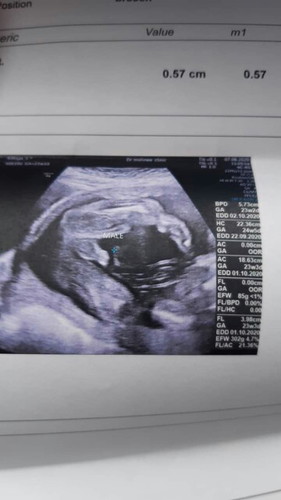

ตอนนี้ได้23สัปดาห์แล้วค่ะ น้องดิ้นเก่งมาก เพิ่งไปซาวด์มาได้ ได้ผู้ชาย คนแรกได้ผู้หญิง เตรียมปิดอู่ แต่แอบกังวลว่าถ้าทำหมันมีผลทำให้อ้วนมั้ยค่ะขอสอบถามหน่อยค่ะ ใครพอจะทราบมั้ย?